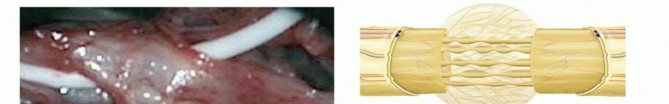

EXTERNAL NEUROLYSIS

External neurolysis is defined as the circumferential freeing of a peripheral nerve from surrounding scar tissue (TECH FIG 1A). Dissection proceeds from normal nerve (both proximal and distal) to the area of scarring (TECH FIG 1B).

TECH FIG 1 • External neurolysis and xenograft nerve wrap. A. The median nerve at the wrist developed painful scarring after carpal tunnel release. B. External neurolysis has been performed by excision of all scar tissue and thickened epineurium. C. A xenograft collagen nerve wrap has been placed around the nerve to minimize scar tissue formation around the nerve. The nerve should be mobilized away from the scar tissue bed to prevent recurrence. Use of a xenograft nerve wrap or fat graft may be considered to prevent recurrence of scarring (TECH FIG 1C). External neurolysis may relieve neuropathic pain associated with compression, but results for sensory and motor recovery are variable.